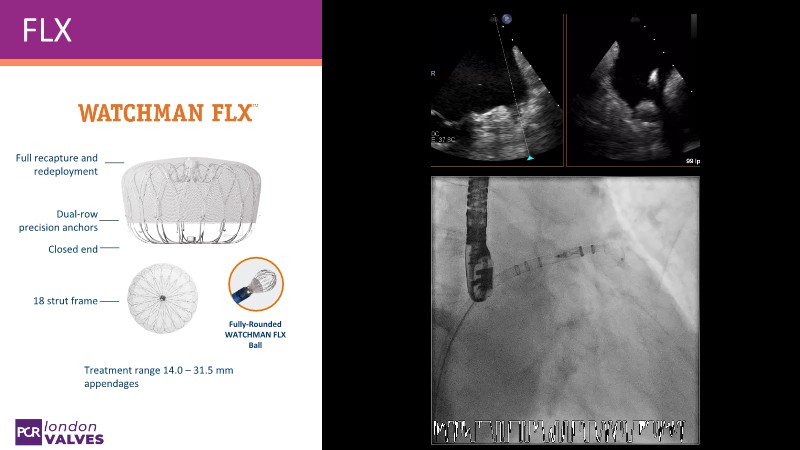

Explore the forefront of left atrial appendage (LAA) closure with this session focusing on the latest innovations and clinical opportunities. Topics include recent data on WATCHMAN FLX PRO and VersaCross Connect systems, workflow strategies to improve procedural efficiency, and discussions on upcoming clinical trials such as CHAF and LAAOS IV, emphasizing expanding stroke prevention options beyond bleeding risk reduction.

- To review the latest data on WATCHMAN FLX PRO and VersaCross Connect - HEAL LAA and subanalysis

- To learn workflow strategies to improve efficiencies for LAA closure - VersaCross Connect + PRO + TruSteer